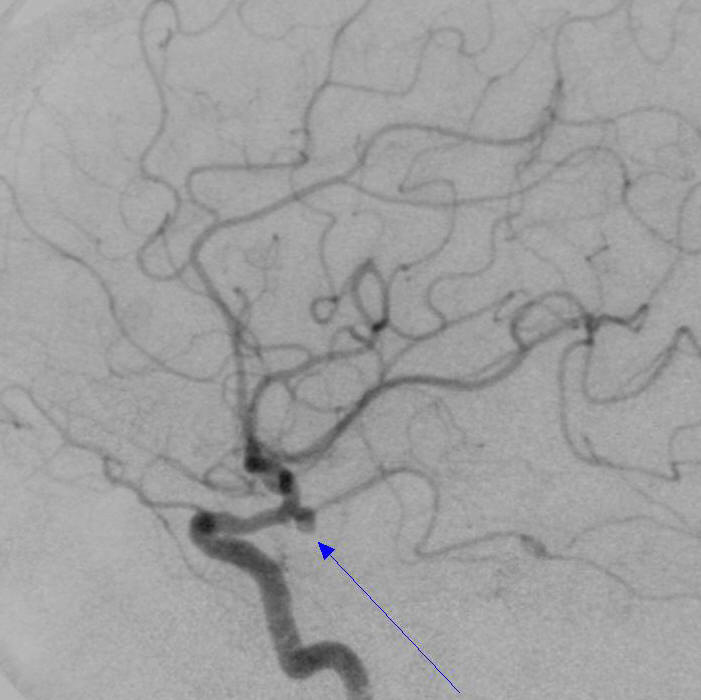

病例3